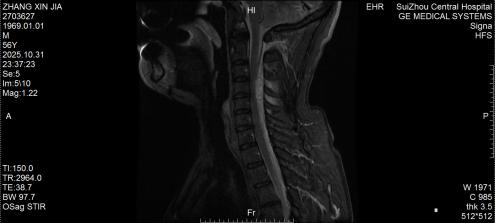

圖1:術(shù)前MRI見椎管內(nèi)積血壓迫脊髓

圖2:術(shù)后MRI見脊髓壓迫解除